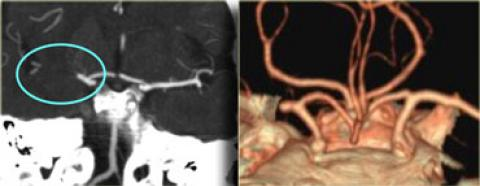

4.1.2. CT mạch máu đầu cổ (CTA)

Cho thấy tắc nghẽn, hẹp mạch máu cũng như tình tràng tuần hoàn nối, bàng hệ.

Hình ảnh tắc động mạch não giữa MCA bên phải trên CTA